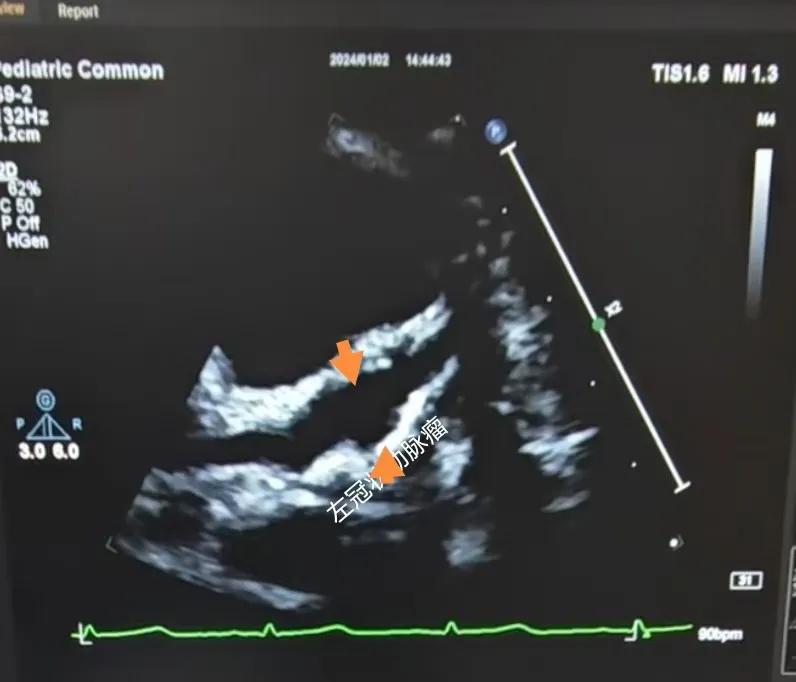

(川崎病患兒:左冠狀動(dòng)脈瘤)

川崎病是兒童時(shí)期一種急性全身非特異性血管炎,對(duì)心臟的損害主要是冠狀動(dòng)脈,可導(dǎo)致冠狀動(dòng)脈的擴(kuò)張、冠狀動(dòng)脈瘤及冠狀動(dòng)脈血栓,這些損傷可能會(huì)引起心肌梗死,目前川崎病已經(jīng)成為兒童獲得性心臟病的主要原因。心臟超聲診斷川崎病,特別是在臨床癥狀不典型或?qū)嶒?yàn)室檢查結(jié)果不明確的情況下。通過(guò)心臟超聲,可以觀察到冠狀動(dòng)脈的擴(kuò)張情況,這是診斷川崎病的一個(gè)關(guān)鍵指標(biāo)。心臟超聲能夠精確測(cè)量冠狀動(dòng)脈的內(nèi)徑及擴(kuò)張程度,對(duì)于診斷冠狀動(dòng)脈瘤形成具有特異性。這對(duì)于早期診斷和及時(shí)治療至關(guān)重要。還可以檢測(cè)到心臟其他一些并發(fā)癥,如心肌病、心包炎和心律失常等??梢栽u(píng)估心臟的整體功能和心肌運(yùn)動(dòng)狀態(tài),這有助于判斷疾病的嚴(yán)重程度和治療效果。在疾病的恢復(fù)期,可以用于監(jiān)測(cè)冠狀動(dòng)脈的恢復(fù)情況,并及時(shí)發(fā)現(xiàn)可能的復(fù)發(fā)或新的并發(fā)癥。

川崎病的超聲診斷標(biāo)準(zhǔn):

B.冠狀動(dòng)脈瘤:冠狀動(dòng)脈內(nèi)徑>4mm,其與主動(dòng)脈根部?jī)?nèi)徑之比>0.3。